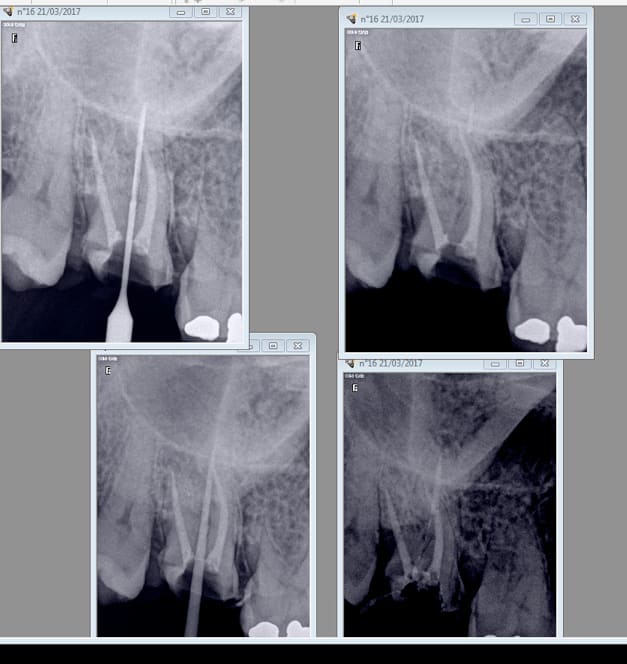

Par contre faut se méfier avec les largo 1. J'ai foré jusqu'à 3 mm de l'apex ( pas moyen de mettre un stop trop fin) , obligé de ré-obturer pour rattraper le coup. -)

Tiencasa c'est à l'aise une endo. Tu ouvres la chambre, tu y colles de l'hypochrorite ensuite tu picores au sx au pif pour trouver les canaux et tu alternes SX-R25. Ensuite tu ouvres légèrement au largo 3. Ca prends 2 minutes et la moitié du boulot est fait. -)

Ensuite tu fais la meme chose avec le R25 et le S1 et 2 minutes après tu es à l'apex en 25 conicité 6. Je parle pour les 3 canaux bien sur. Ici pas trouvé de MV2 mais c'est rare.

Si ca te permet de laisser tomber tes limes K ca sera déjà pas mal. Bon ensuite tu deviens moins conservateur......-)))).